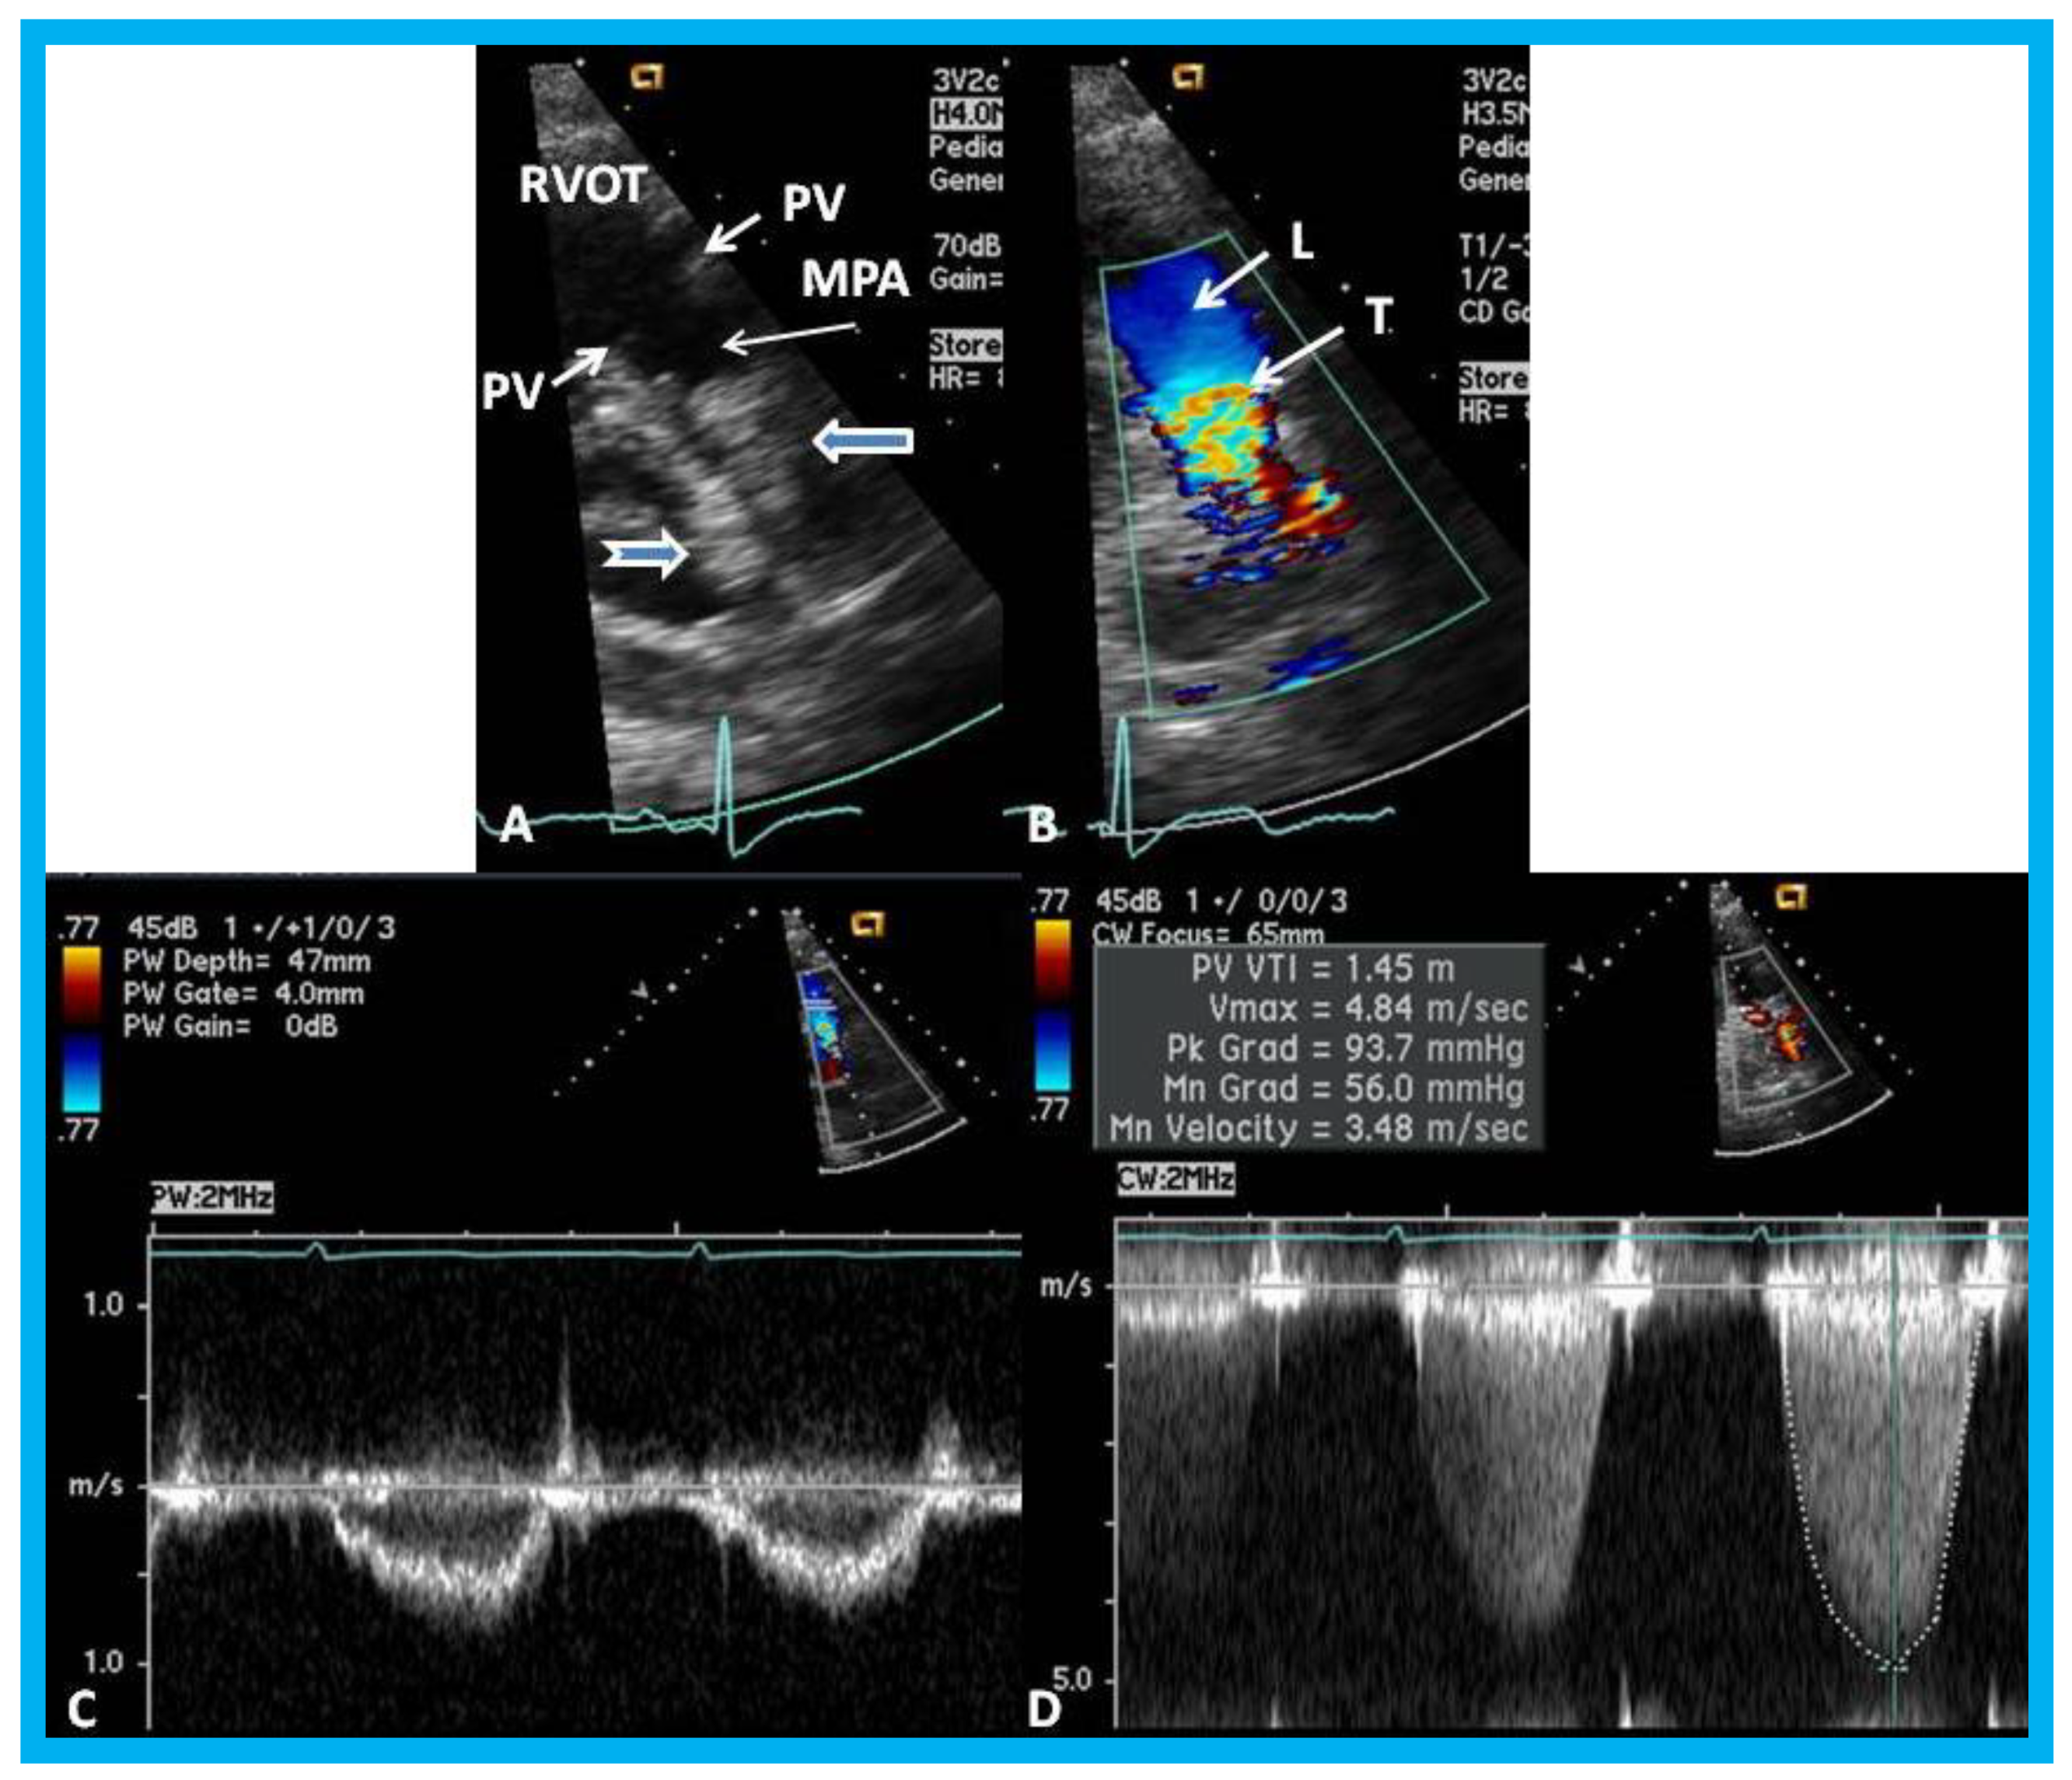

Figure 21. (A) Selected video frame from a parasternal short axis view showing echo dense structures (thick blue arrows) within and outside the main pulmonary artery (MPA): Pulmonary valve (PV) leaflets (small arrows) are shown and appear normal. The right ventricular outflow tract (RVOT) and proximal MPA are free of any echo-dense structures. (B) Color-Doppler mapping of the same structures as in panel A shows normal laminar (L) flow in the RVOT and proximal MPA and turbulent (T) flow starting in the proximal MPA, indicating obstruction. (C) Pulse Doppler sampling from the proximal MPA, which shows normal flow velocity. (D) Continuous wave Doppler sampling demonstrating high velocity flow across the MPA with a calculated peak instantaneous gradient of 93.7 mmHg and a mean gradient of 56 mmHg, indicating severe obstruction. Reproduced from Mazur L., et al. [31].

Children 07 00034 g021

An eleven-year-old female patient had a Nuss procedure for treatment of pectus excavatum [30]. A cardiac murmur was heard shortly before the planned Nuss bar removal at the age of thirteen years. Echocardiographic evaluation revealed external compression (Figure 21), causing supravalvar pulmonary stenosis [31]. Removal of the Nuss bar was performed which documented improvement on echo-Doppler studies (Figure 22). Usefulness of echo studies in evaluation of such issues was emphasized.